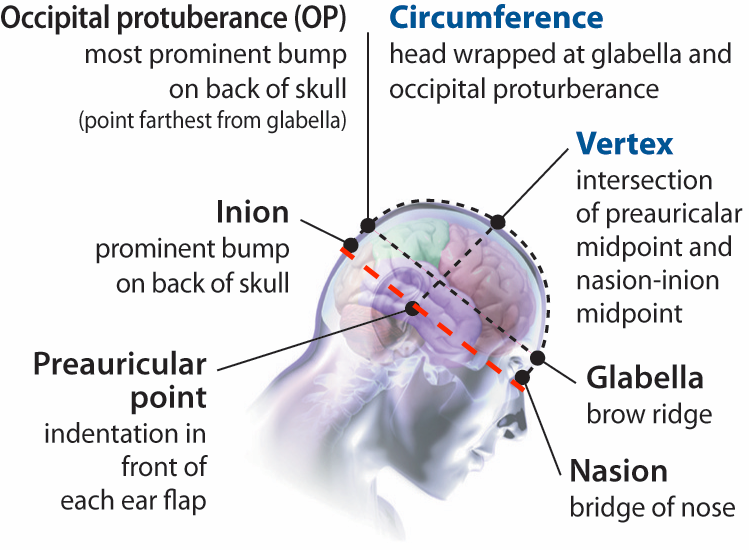

The canthomeatal line is also referred to as the orbitomeatal line and is defined as running from the lowermost point of the eye’s bony orbit to the preauricular point. In the image below the canthomeatal line is indicated by the red dashed line:

In 10-20 EEG placement, electrodes (typically 19-21 electrodes) all are placed above the cantomeatal line.